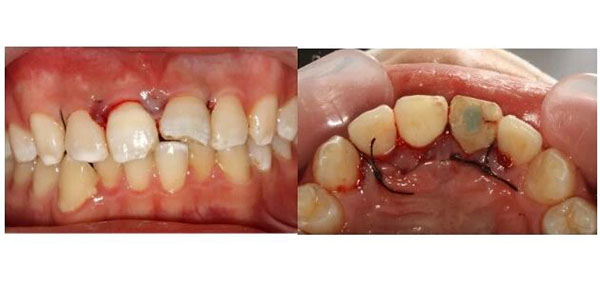

术后1周拆线,伤口长得不错。

术后2周,完成冠部的充填修复。

最后,口腔急诊医生选择了一条更有挑战的路——在牙周翻瓣手术下,把折断的牙齿“接”回去:

先完成根管治疗,把牙齿内部清理干净。然后,在手术显微镜下,翻开牙龈,暴露出深藏在牙槽骨里的断端,用纤维桩像“钢筋”一样打进牙根里,再把断下来的牙冠原样粘回去。